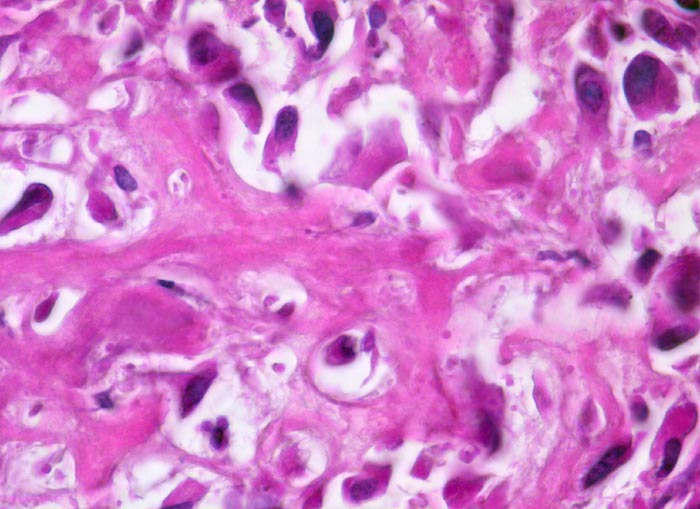

• Tibiametaphyse mit angrenzendem Weichteilgewebe.

• Das Sarkom infiltriert diffus den spongiösen Knochen der Diaphyse und hat präexistente Knochenbälkchen verdrängt.

• Der Tumor hat die Korticalis destruiert und infiltriert die angrenzende Skelettmuskulatur.

• Der Tumor besteht aus neugebildetem bereits verkalktem Knochen oder einem Netzwerk von primitiven Osteoidtrabekeln. Entlang oder innerhalb der Osteoidtrabekel lokalisierte polymorphe Tumorzellen mit ausgeprägten Kernatypien und zahlreichen Mitosen. Leicht verwaschene Kernstrukturen als Folge der Gewebsentkalkung.